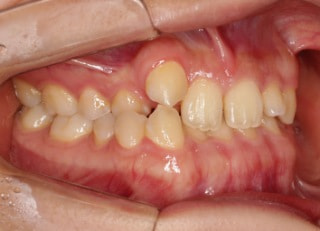

治療開始から25ヶ月後